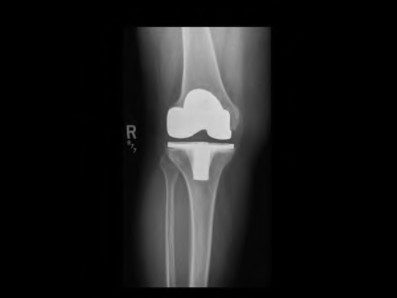

A 67-year-old diabetic male presents 4 months status post right total knee arthroplasty (TKA) complaining of pain and stiffness for the last four weeks. A clinical photograph is shown in Figure A. Radiographs and a bone scan are shown in Figures B, C and D. Blood work shows an ESR of 14mm/hr (normal 0-12mm/hr) and a CRP of 2mg/L (normal 1-3mg/L). Knee aspiration yields WBC of 1000, 30% PMNs, and a negative gram stain. He finished a 14-day course of antibiotics prescribed to him by his primary care physician one week ago. Which of the following is the most appropriate next step in management?

The work-up of a suspected PJI after TKA includes an evaluation of radiological (x-ray +/- bone scan and PET scan) and laboratory (ESR and CRP) parameters as well as analysis of joint aspirate fluid (cell count and differential, culture, gram stain +/- PCR).

Figure A is a clinical photograph demonstrating a swollen, erythematous right knee with a well-healed incision from a previous TKA. Figure B and C are AP and lateral radiographs of the right knee with no obvious acute findings. Figure D is a bone scan demonstrating increased uptake in the post-operative knee, which is consistent with the 4 month follow-up.